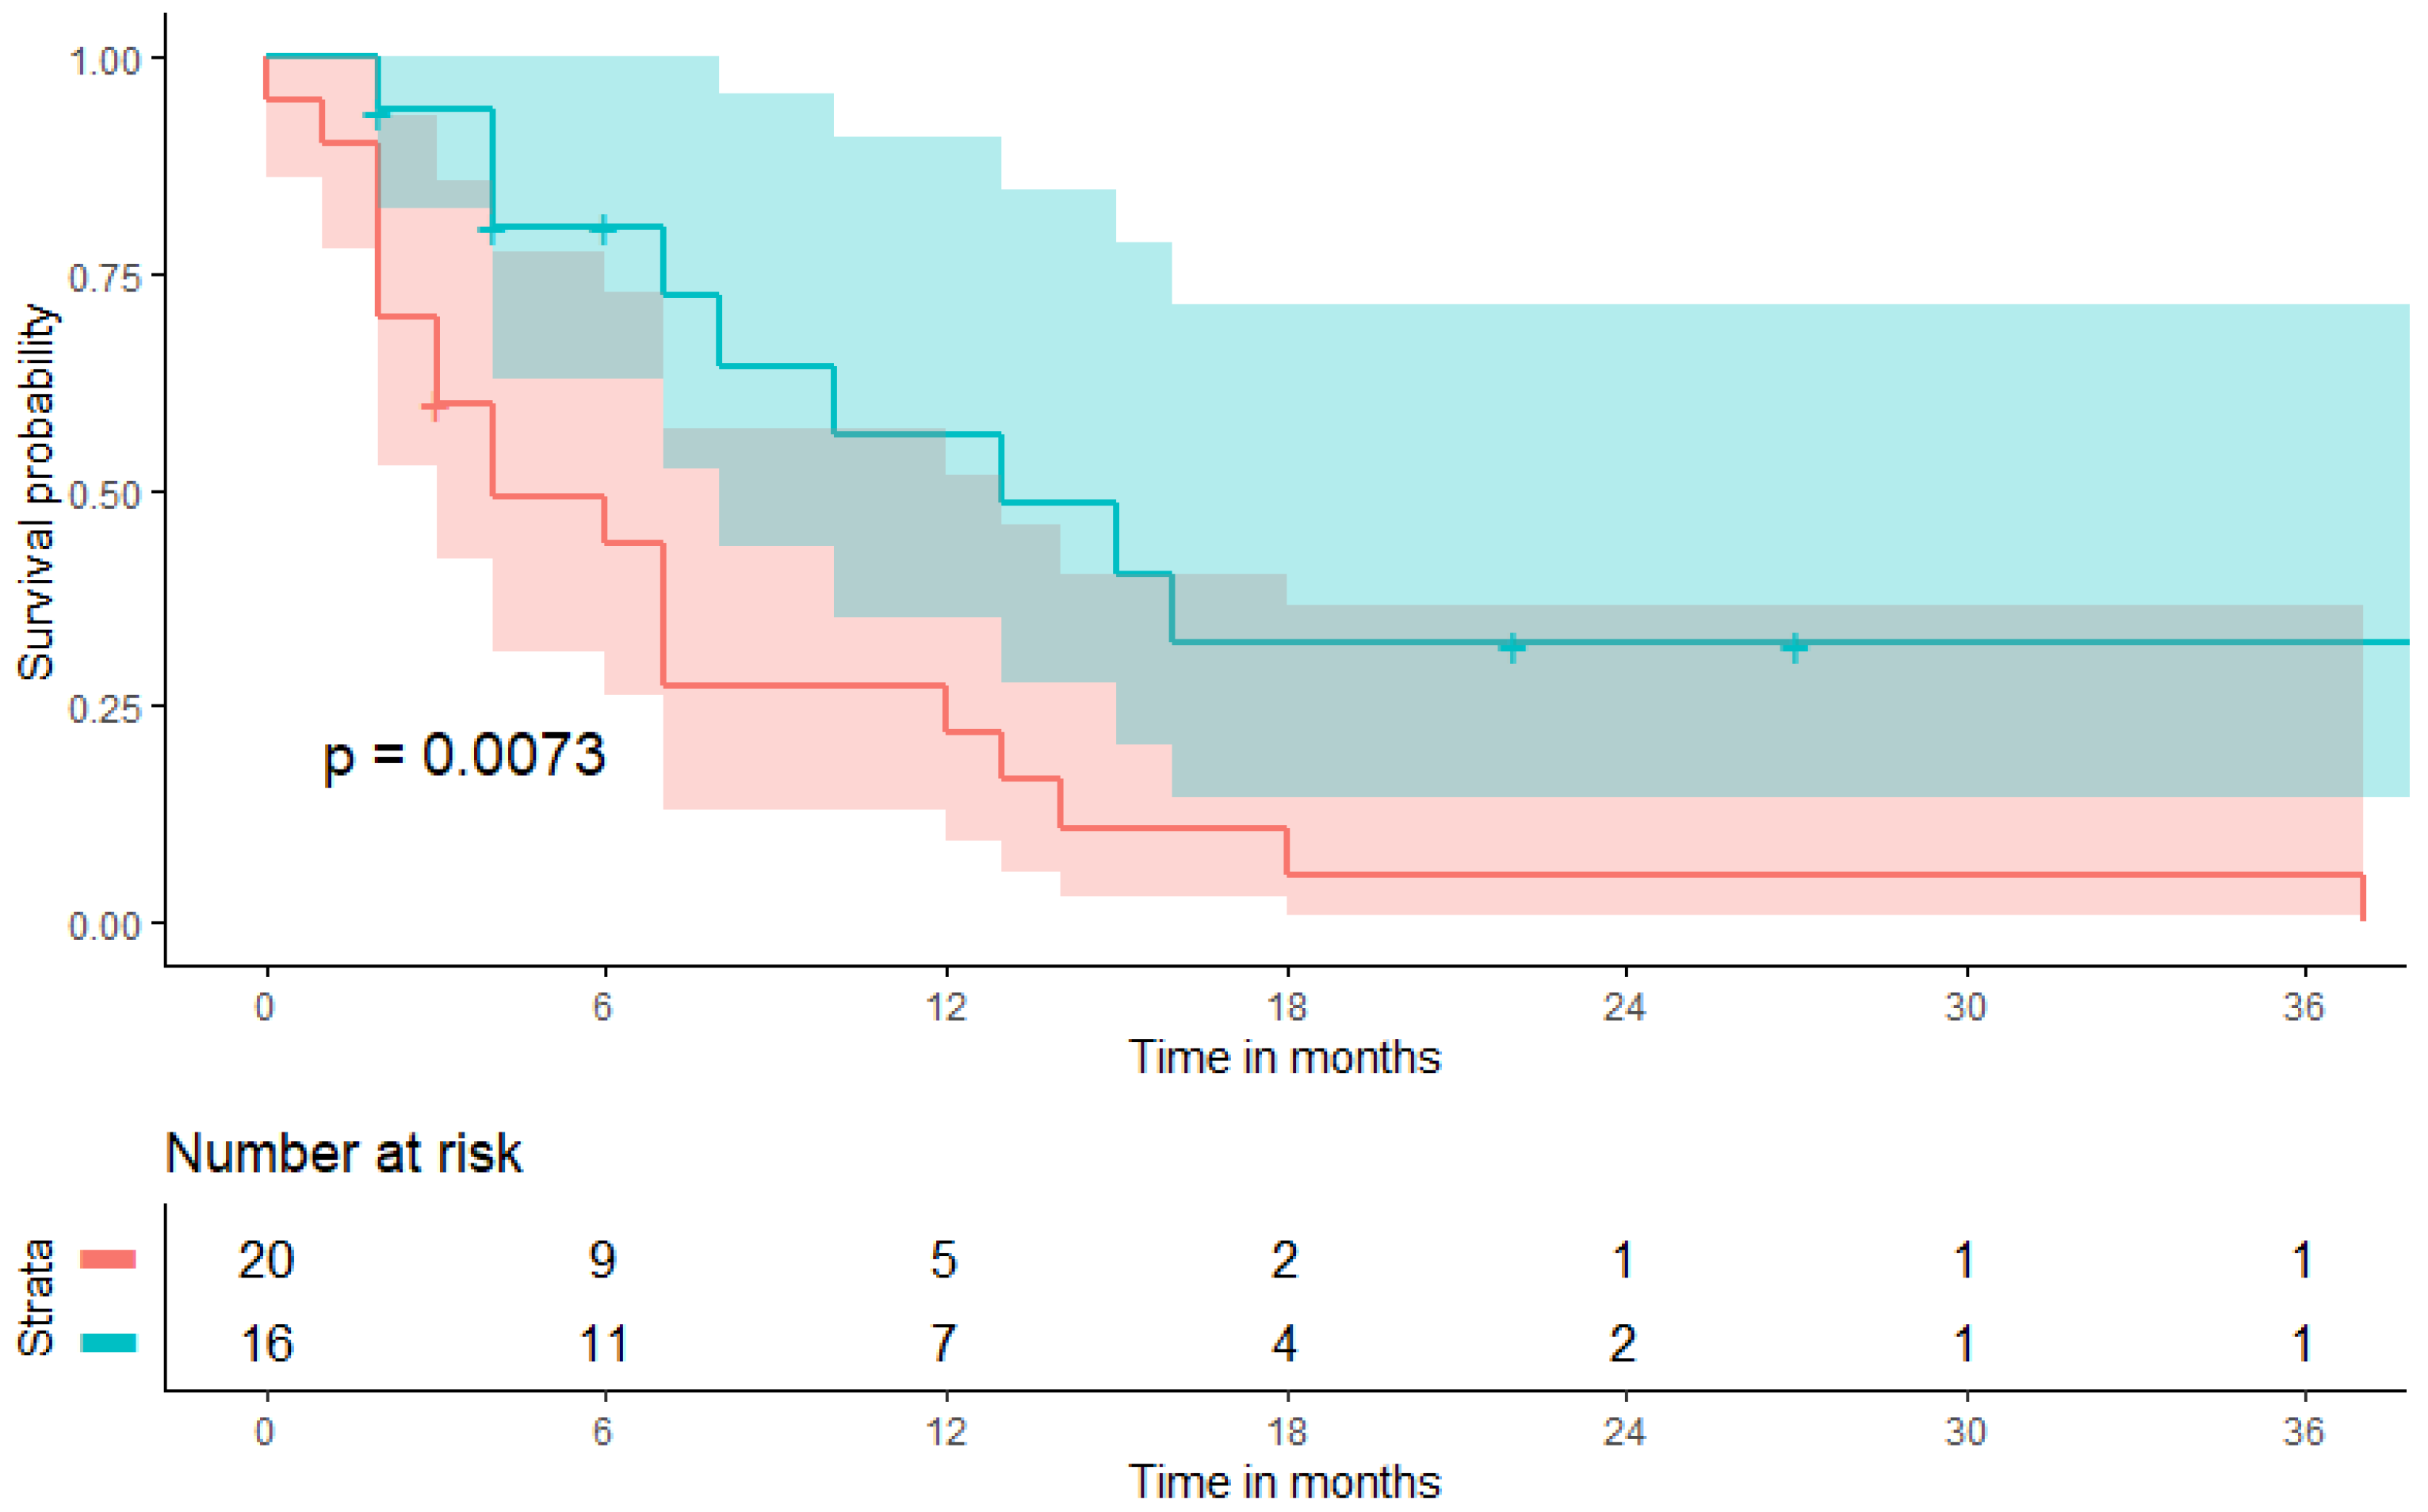

3.3. Prognostic Value of a Pretherapeutic BMI on Patient Survival during CPI Therapy

| progression-free survival (PFS, months) | 6.5 (3.0–13.8) | 4.0 (2.0–10.8) | 9.0 (4.0–20.5) | 0.102 * |

| overall survival (OS, months) | 9.5 (4.3–18.8) | 7.0 (4.3–15.8) | 13.5 (4.5–22.0) | 0.499 * |

| body mass index (5 kg/m2 increment) | 0.038 | 1.54 (1.03–2.34) | 0.002 | 3.73 (1.63–8.50) |

| body mass index (5 kg/m2 increment) | 0.028 | 1.87 (1.07–3.29) | 0.010 | 7.44 (1.62–34.16) |